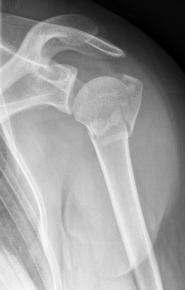

Proximaler Oberarmbruch7Proximaler Oberarmbruch8

Picture: In the above pictures, a slightly shifted subcapital humeral fracture was internally splinted using intramedullary nail. The left picture is a follow-up examination half a year after the accident and shows the complete healing of the fracture with correct position of the bone.